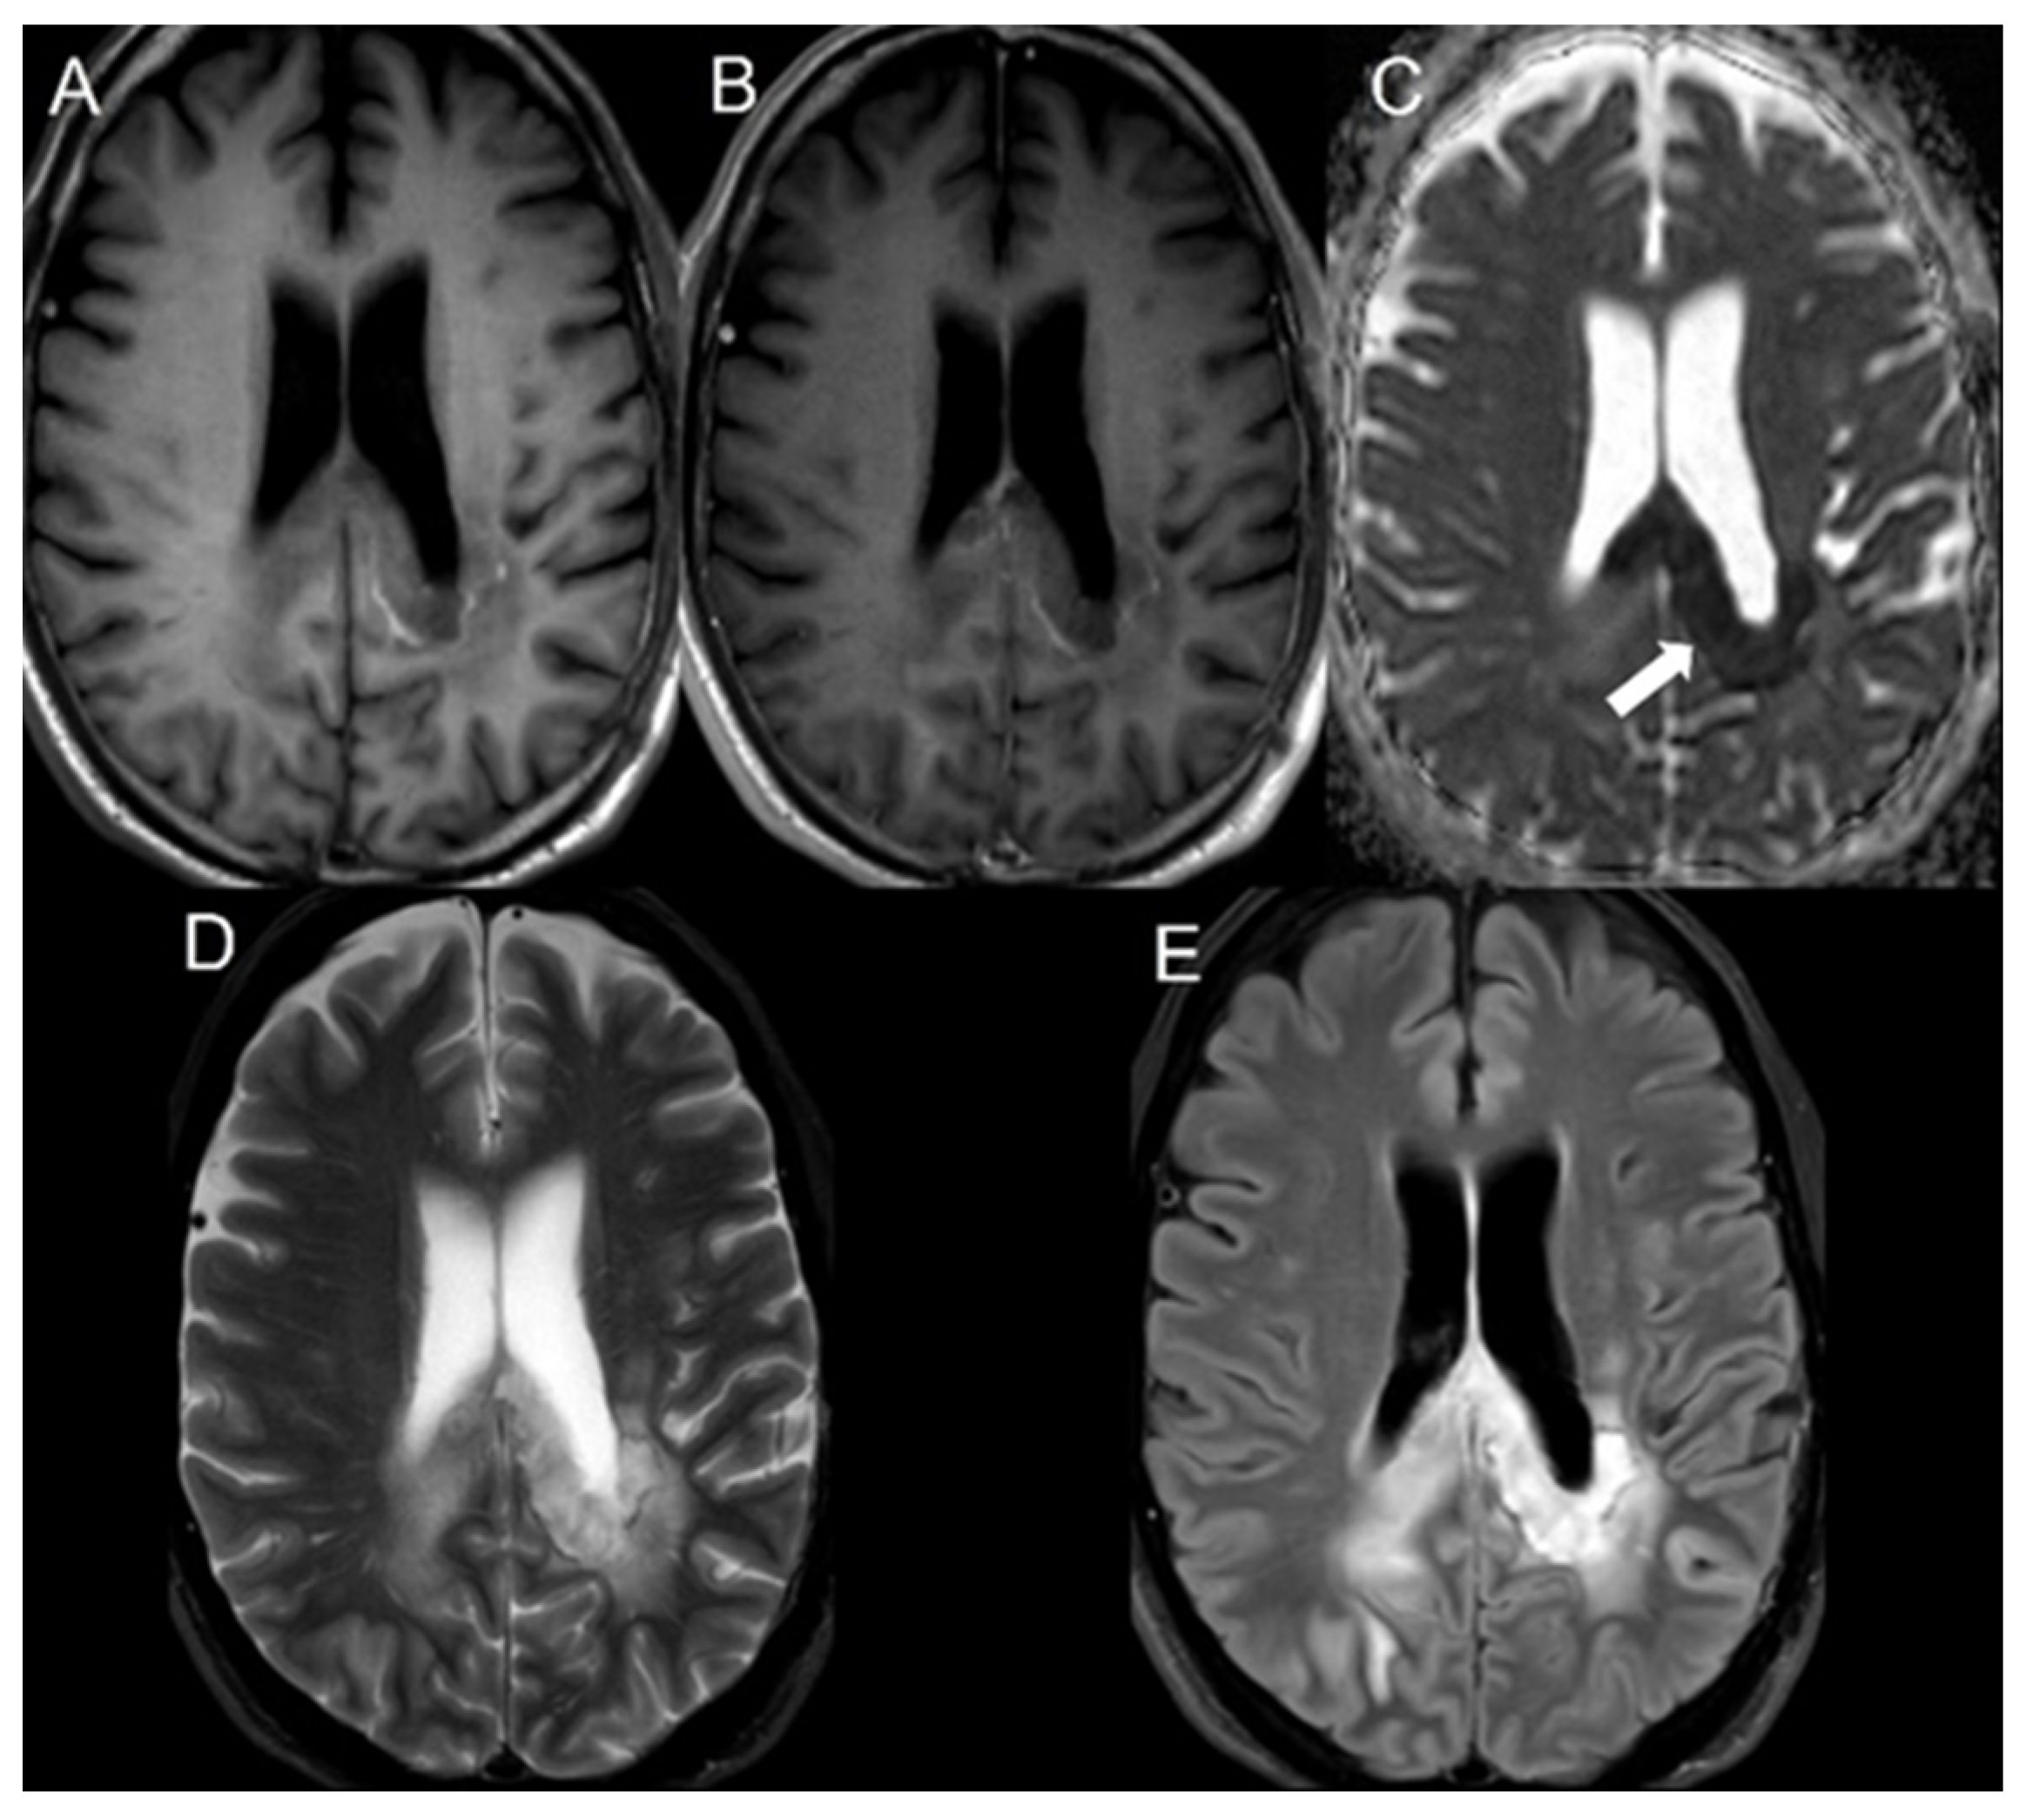

| Patient No. | Age at Death | Tumor Type | Surgery | XRT | TMZ | Location of Focal Region of Diffusion Restriction | Bevacizumab (Day) before Death | Bevacizumab (Day) before Focal Region Appears | Days between Focal Region and Death |

|---|---|---|---|---|---|---|---|---|---|

| 1 | Still alive | GBM | + | + | + | CC | N/A | 181 | N/A |

| 2 | 32 | GBM | + | + | + | CC | 90 | 74 | 16 |

| 3 | 45 | GBM | + | + | + | CC | 574 | 61 | 513 |

| 4 | 77 | GBM | + | + | + | CR | 424 | 58 | 366 |

| 5 | 57 | GBM | + | + | + | CC | 647 | 339 | 308 |

| 6 | Still alive | GBM | + | + | + | CC | N/A | 258 | N/A |

| 7 | 48 | GBM | + | + | + | PV | 283 | 16 | 267 |

| 8 | 68 | GBM | + | + | + | CR | 92 | 34 | 58 |

| 9 | 67 | GBM | + | + | + | CR | 573 | 150 | 423 |

| 10 | 64 | GBM | + | + | + | PV | 589 | 25 | 564 |

| 11 | 57 | GBM | + | + | + | CC | 281 | 57 | 224 |

| 12 | 67 | GBM | + | + | + | CC | 75 | 41 | 34 |

| 13 | 65 | GBM | + | + | + | PV | 272 | 90 | 182 |

| 14 | 48 | GBM | + | + | + | PV | 717 | 371 | 346 |

| 15 | 51 | GBM | + | + | + | CC | 229 | 41 | 188 |

| 16 | 72 | GBM | + | + | + | PV | 878 | 49 | 829 |

| 17 | 52 | GBM | + | + | + | CC | 575 | 140 | 435 |

| 18 | 54 | GBM | + | + | + | CC | 651 | 355 | 296 |

| 19 | 83 | GBM | + | + | + | PV | 168 | 36 | 132 |

| 20 | 57 | GBM | + | + | + | PV and CC | 359 | 41 | 318 |

| 21 | 47 | GBM | + | + | + | Parasagittal frontal lobe, cingulate gyrus, CC | 295 | 99 | 196 |